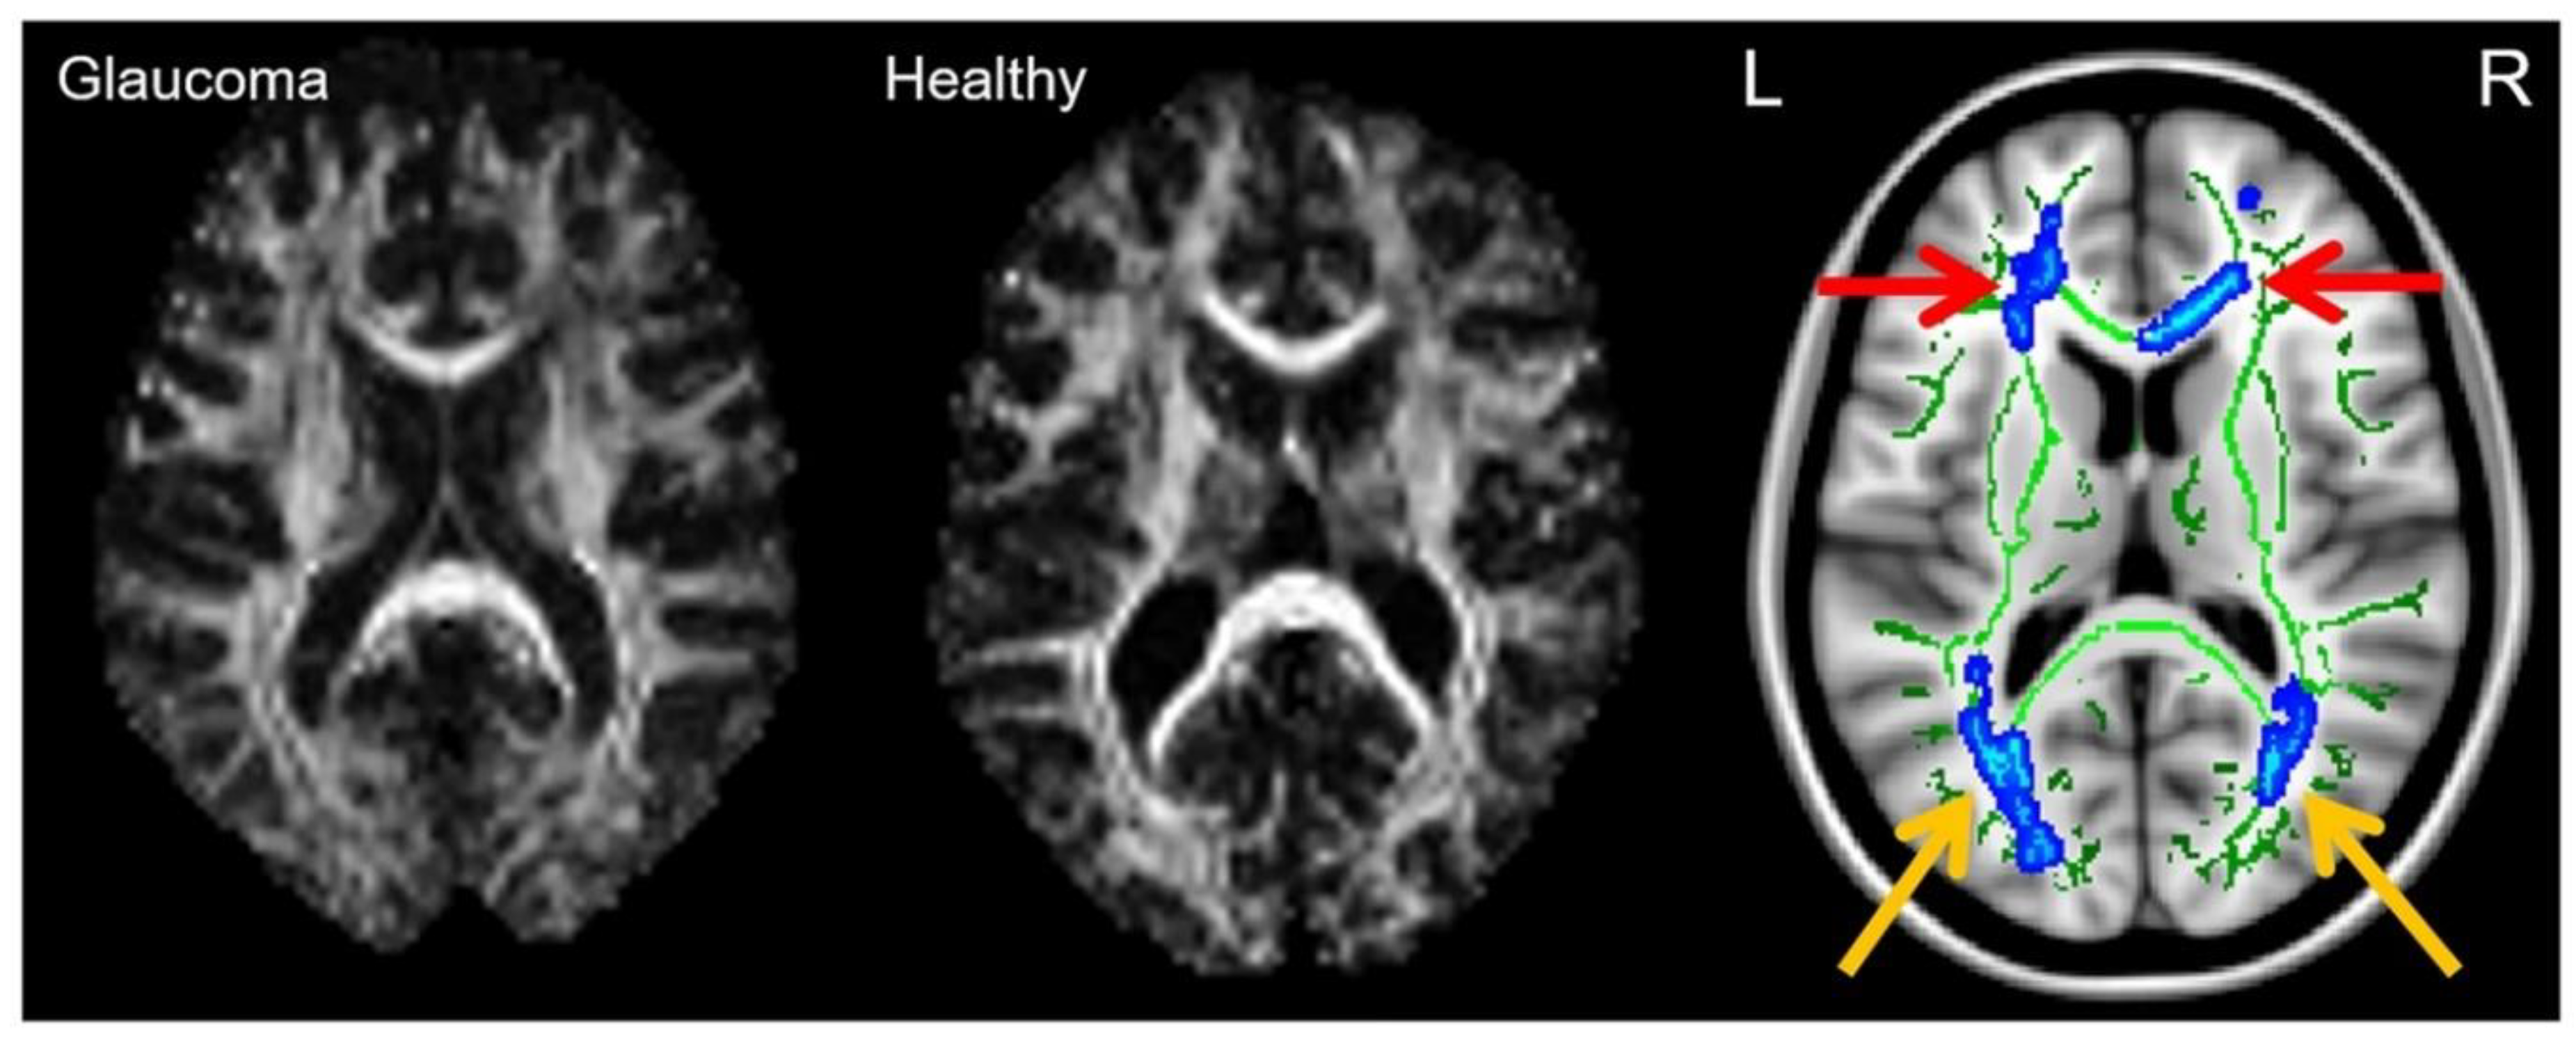

2.4. Diffusion Tensor Imaging (DTI) in Glaucoma

2.7. Diffusion MRI Tractography in Glaucoma